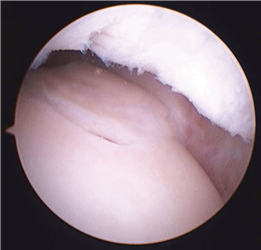

Clinical & Radiographic Imaging Archive